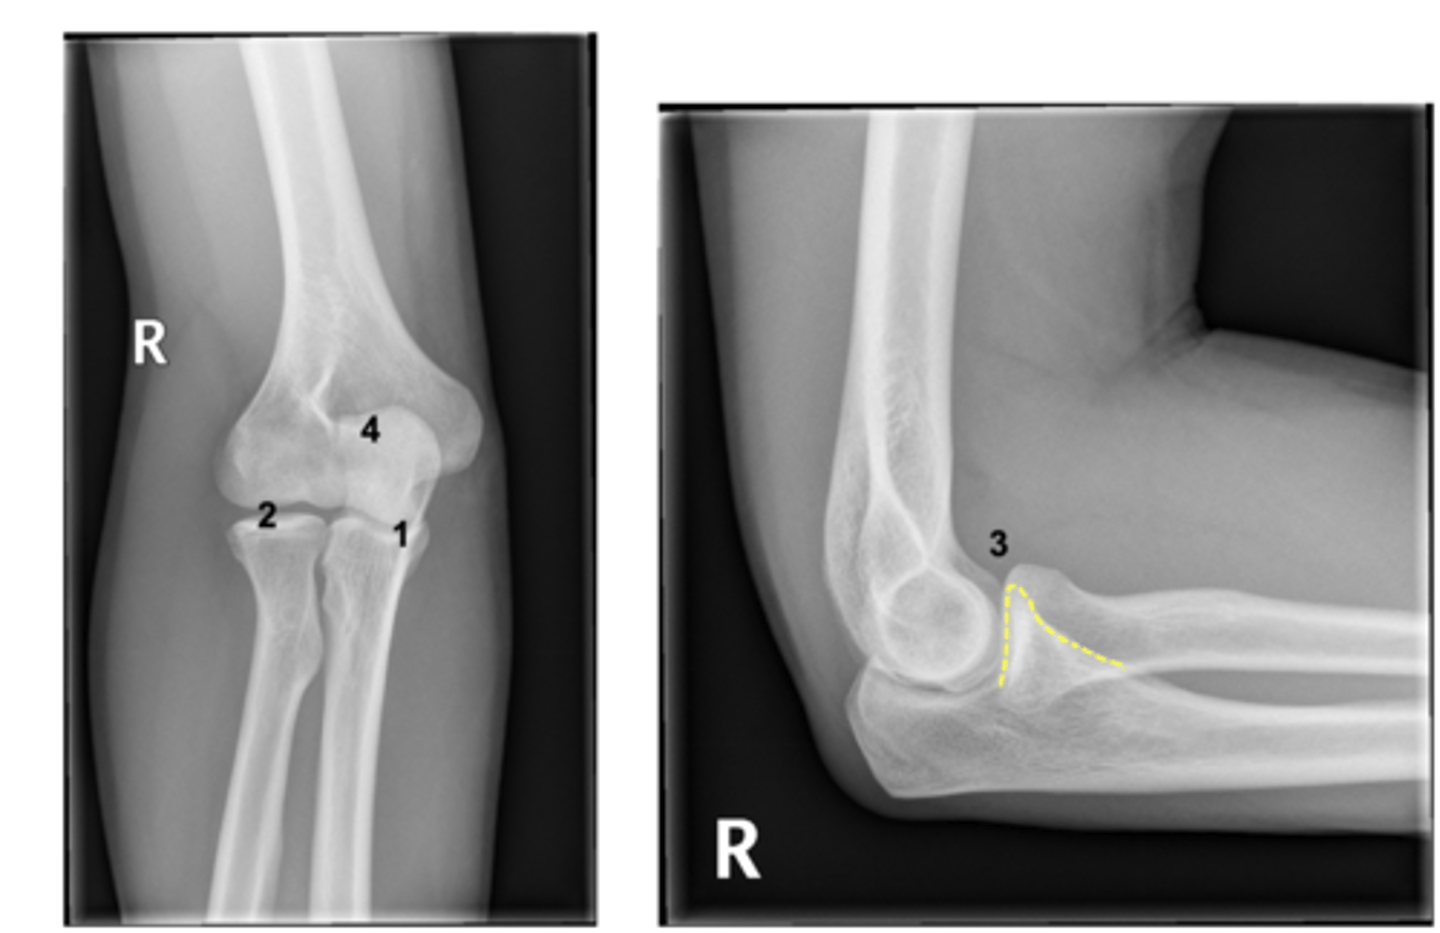

Inverse card: label the image

1. Neck of radius

2. Head of radius

3. Coronoid process

4. Olecranon

5. Medial epicondyle of humerus

6. Trochlea

1. Humeral External Torsion

- humeral shaft is rotated externally around its long axis, aligning the distal humeral condyle close to the coronal plane such that elbow flexion brings the hand anteriorly and toward the clavicle.

2. Anterior curve distal humeral shaft

- The distal shaft curves anteriorly, directing the articular surfaces more anteriorly and thus favouring flexion.

3. Inferomedial joint axis

- medial edge of the trochlea extends farther distally than the lateral, creating an inferomedial joint axis and partly explaining the lateral orientation of the ulna with respect to the humerus.

What three features affect orientation/ROM of the elbow joint?